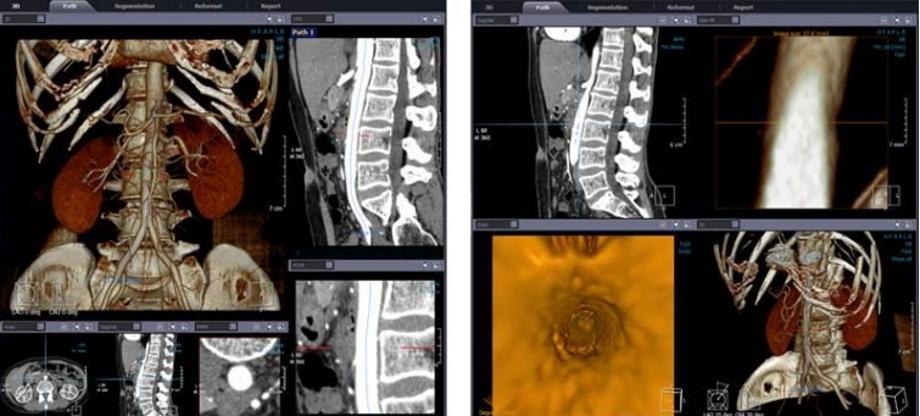

건양대 방사선학과, 학부생 교육 위해 디지털 3D 교육 프로그램 도입 건양대학교(총장 김용하) 방사선학과(학과장 유세종)가 학생교육을 위해 ㈜인피니트테크롤로지의 Xelis 디지털 의료영상 3D 프로그램을 도입했다고 밝혔다. 디지털 의료영상 3D는 병원 사용하는 검사하는 CT, MRI, 초음파 등 검사에서 필수적으로 사용하는 검사 보조 프로그램으로 미세 병변을 찾아내는데 아주 유용하게 사용되고 있다. 건양대 방사선학과는 이번 프로그램 도입을 통해 학생들이 직접 병원 현장에서 쓰이는 프로그램으로 실습을 함으로써 졸업과 동시에 바로 실전에서 환자를 검사할 수 있는 준비된 방사선사를 양성한다는 계획이다. 건양대 방사선학과 유세종 학과장은 “건양대 의과학대학은 2025년 새로운 건물을 완공해 이전할 계획이며 새로운 공간에 걸맞은 최첨단 교육 시스템을 도입할 계획이다”라며 “재학생뿐만 아니라 신규인력 양성과정, 재직자 향상과정 등을 교육할 수 있도록 최고의 교육 장비와 시스템을 완비해 지역 정주형 인력양성을 위해 노력하겠다”고 밝혔다. |